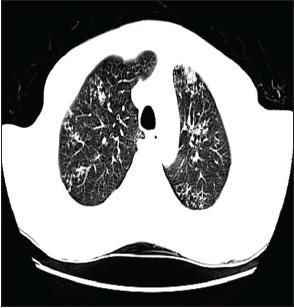

The patient was admitted to the neurosurgical service for brain biopsy. Treatment with dexamethasone was started for CNS edema. ACXR demonstrated a bilateral reticulonodular pattern with upper zone predominance and bilateral hilar predominance (Figure 3). A CT scan of the chest revealed multiple clusters of micronodular opacities in the upper lobes bilaterally and a large area of nodularity with architectural distortion and traction bronchiectasis in the left upper lobe (Figure 4).

Figure 4

This CT scan ofthe chest shows multipleclusters of micronodularopacities in bilateral upperlobes and bronchiectasisand traction in the leftupper lobe.